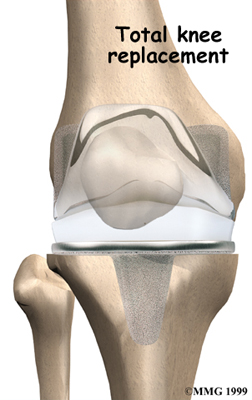

Artificial Knee Replacement

An artificial knee replacement is the ultimate solution for advanced knee OA.

Surgeons prefer not to put a new knee joint in patients younger than 60. This is because younger patients are generally more active and might put too much stress on the joint, causing it to loosen or even crack. A revision surgery to replace a damaged prosthesis is harder to do, has more possible complications, and is usually less successful than a first-time joint replacement surgery.

Related Document: FYZICAL Sun City North's Guide to Artificial Joint Replacement of the Knee